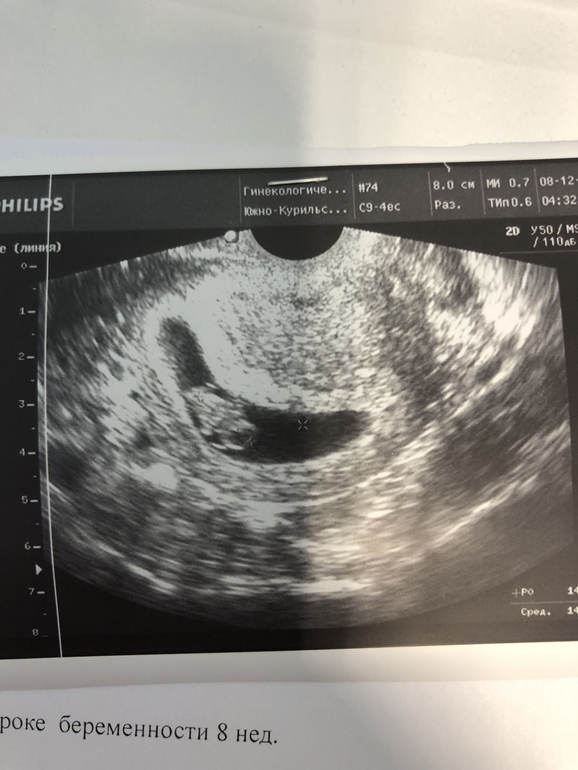

Южно-Сахалинск

У меня такое было, это 8 недель.Кололи ношпу , и покой и с утрожестана зачем то на дюфастон пересадили сказали он лучше.Купите ношпу в таблетках,либо свечи папаверин, но мне больше помогают свечи:)